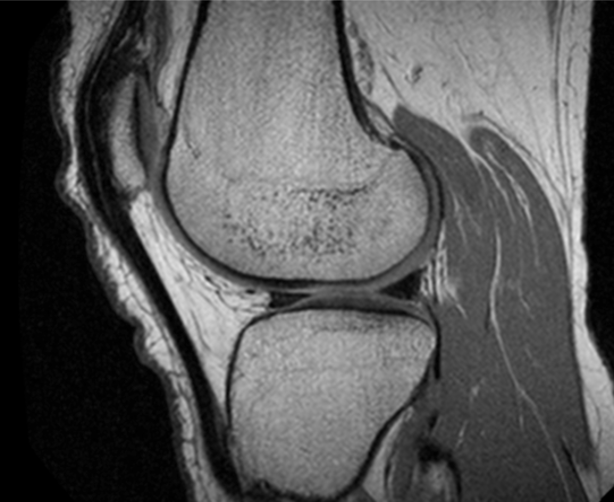

In this study, we use magnetic resonance imaging (MRI) to assess brain metabolites associated with pain and knee health. MRI is non–invasive and does not use ionizing radiation. Knee MRIs are being acquired to best show the structural damage as we expect they will provide more information for research purposes than clinical x-rays. Brain imaging is being acquired to examine differences in the brain that occur with chronic knee osteoarthritis pain (or its recovery) We expect this combined information will provide great insight to knee osteoarthritis pain.